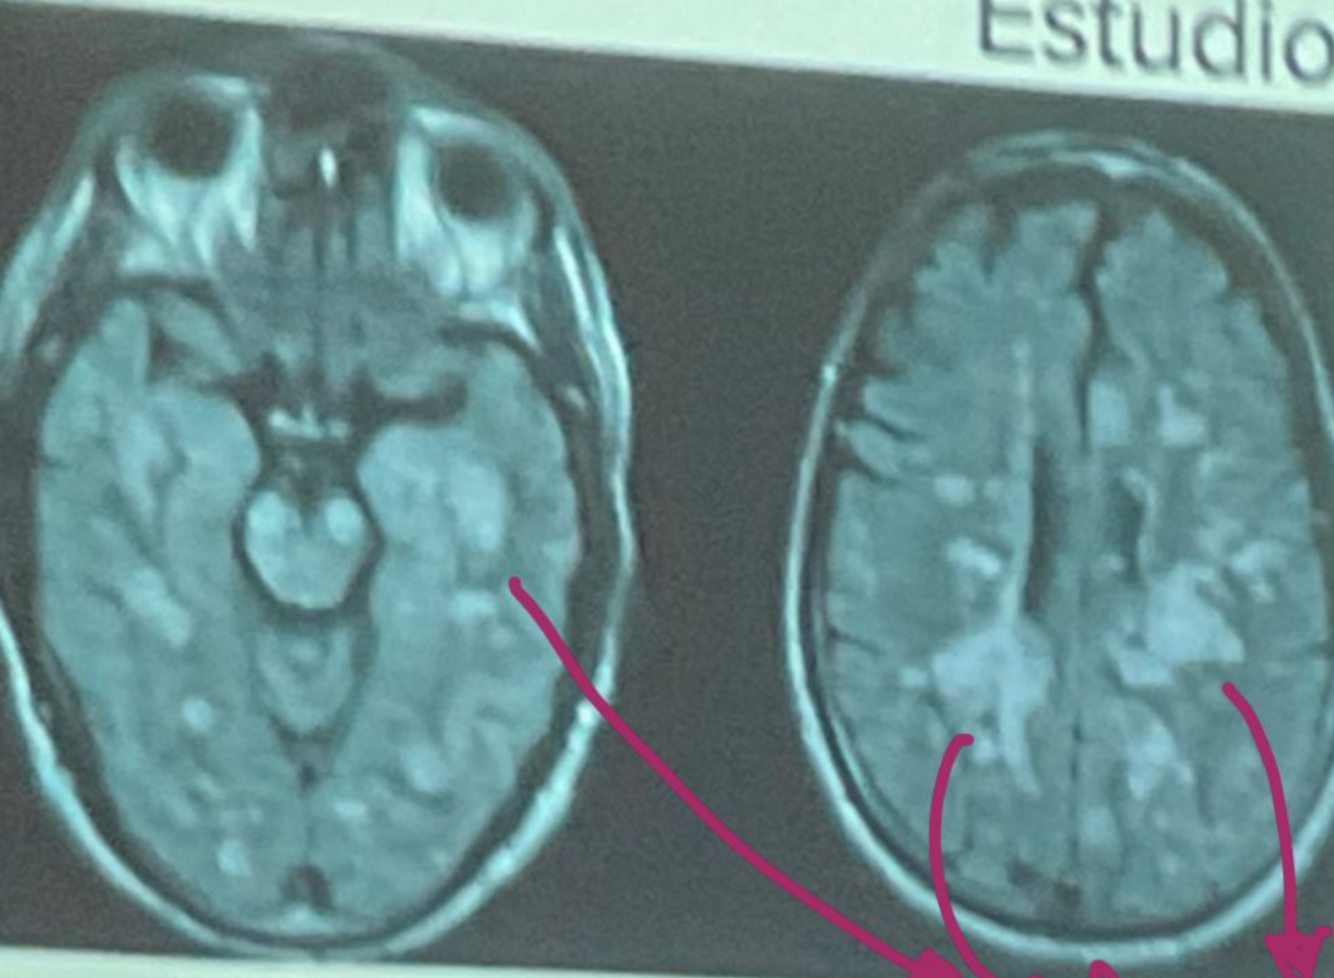

Esta resonancia corresponde a ADEM/EM

EM

ADEM

En la resonancia magnetica la esclerosis multiple da estos signos:

Hiperintensidad en T2 y FLAIR

Hipointensidad en T1

Lesiones redondas y ovaladas, bordes definidos menores a 5mm